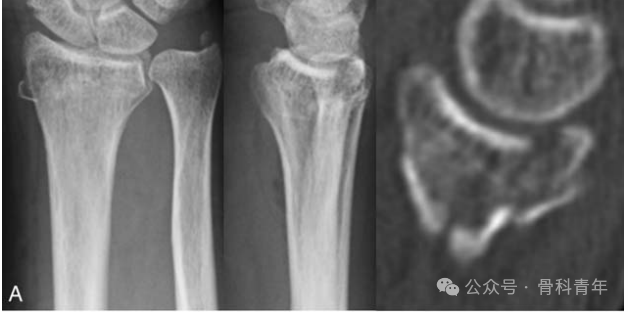

病例示例: